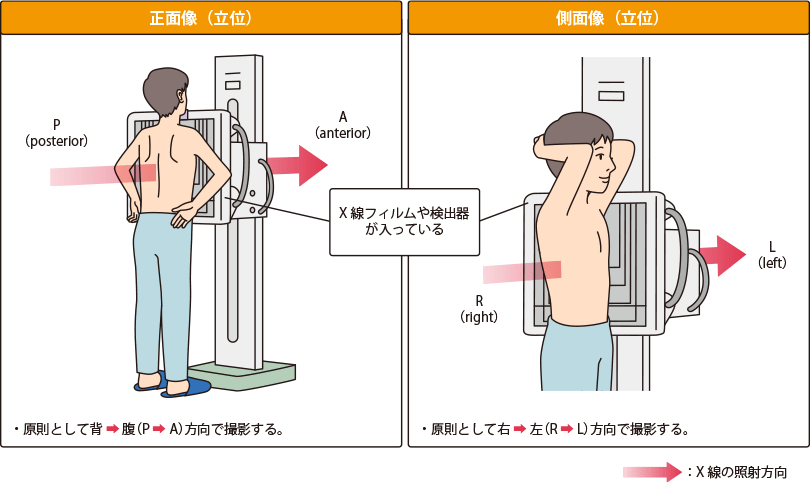

肺がんのレントゲン(X線)検査

胸部X線(レントゲン)検査の撮影法と仕組み

レントゲン検査とは、画像診断の1つであり、肺のX線写真を撮影し、がんを示す陰影がないかを調べる検査です。肺がん診療の最も基本的な検査で、簡便で被ばく量も少ないため、広く普及しています。

撮影法

通常、立位で胸部の正面や側面からX線を当てて撮影します。X線は人体を透過する際に骨や臓器などのさまざまな組織に吸収されるため、フィルムには透過後のX線が検出されます。X線像は組織性状ごとのX線透過性(吸収度)の差を白〜黒の色調で表したもので、大きく4つに分けられます。

胸部単純X線検査では、立体である肺を一方向から平面の写真に投影するため、骨、心臓、血管、横隔膜などの臓器の影に重なって見えにくい部分がかなり大きく存在します。

一方、胸部CT検査では、多方面からX線を照射してX線吸収度(CT値)を測定し、それをもとにコンピュータで画像化することができます。そのため、体の断面を描いたり、得られた写真から立体構成を描いたりすることが可能で、がんの大きさ、性質、周囲の臓器への広がりなど、胸部X線検査よりも多くの情報を得ることができます。

ただし、胸部CT検査では胸部X線検査よりも被曝量が多くなります。

通常、立ったまま背中からX線を当てる正面像、腕を上げて体の横からX線を当てる側面像を撮影します。これら2つの写真を併せることで、肺をより立体的にとらえることができます。